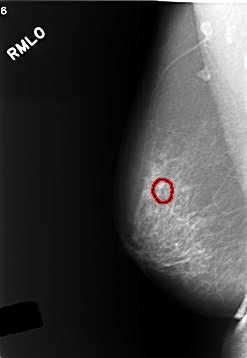

C_0412_1.RIGHT_MLO

FILE: C_0412_1.RIGHT_MLO.OVERLAY

TOTAL_ABNORMALITIES 1

ABNORMALITY 1

LESION_TYPE CALCIFICATION TYPE PLEOMORPHIC DISTRIBUTION CLUSTERED

ASSESSMENT 3

SUBTLETY 3

PATHOLOGY BENIGN

TOTAL_OUTLINES 1

BOUNDARY